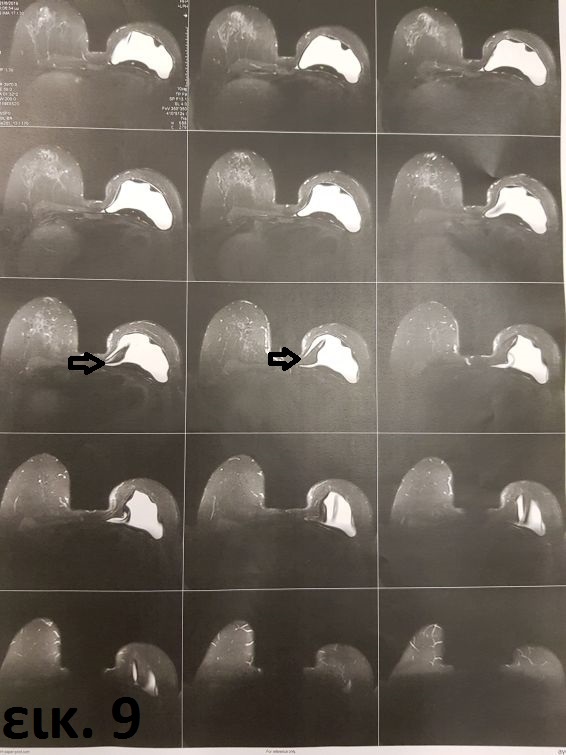

Η δεύτερη ασθενής υπεβλήθη επίσης προ 20ετίας σε αριστερή μαστεκτομή και τοποθέτηση μόνιμου ενθέματος. Τα συμπτώματα ξεκίνησαν περίπου 12 χρόνια αργότερα ως ήπια ενόχληση, ενώ η μαγνητική τομογραφία στην οποία υπεβλήθη λόγω ψηλαφητής σκληρίας στον έσω πόλο κατέδειξε ρήξη του ενθέματος με μικροδιαφυγή σιλικόνης ενδοκαψικά (εικ. 9).

Εικόνα 7: προεγχειρητικό προφίλ, εικόνα 8: αντίστοιχη μετεγχειρητική, εικόνα 10: σημείο διαφυγής σιλικόνης παλιού ενθέματος